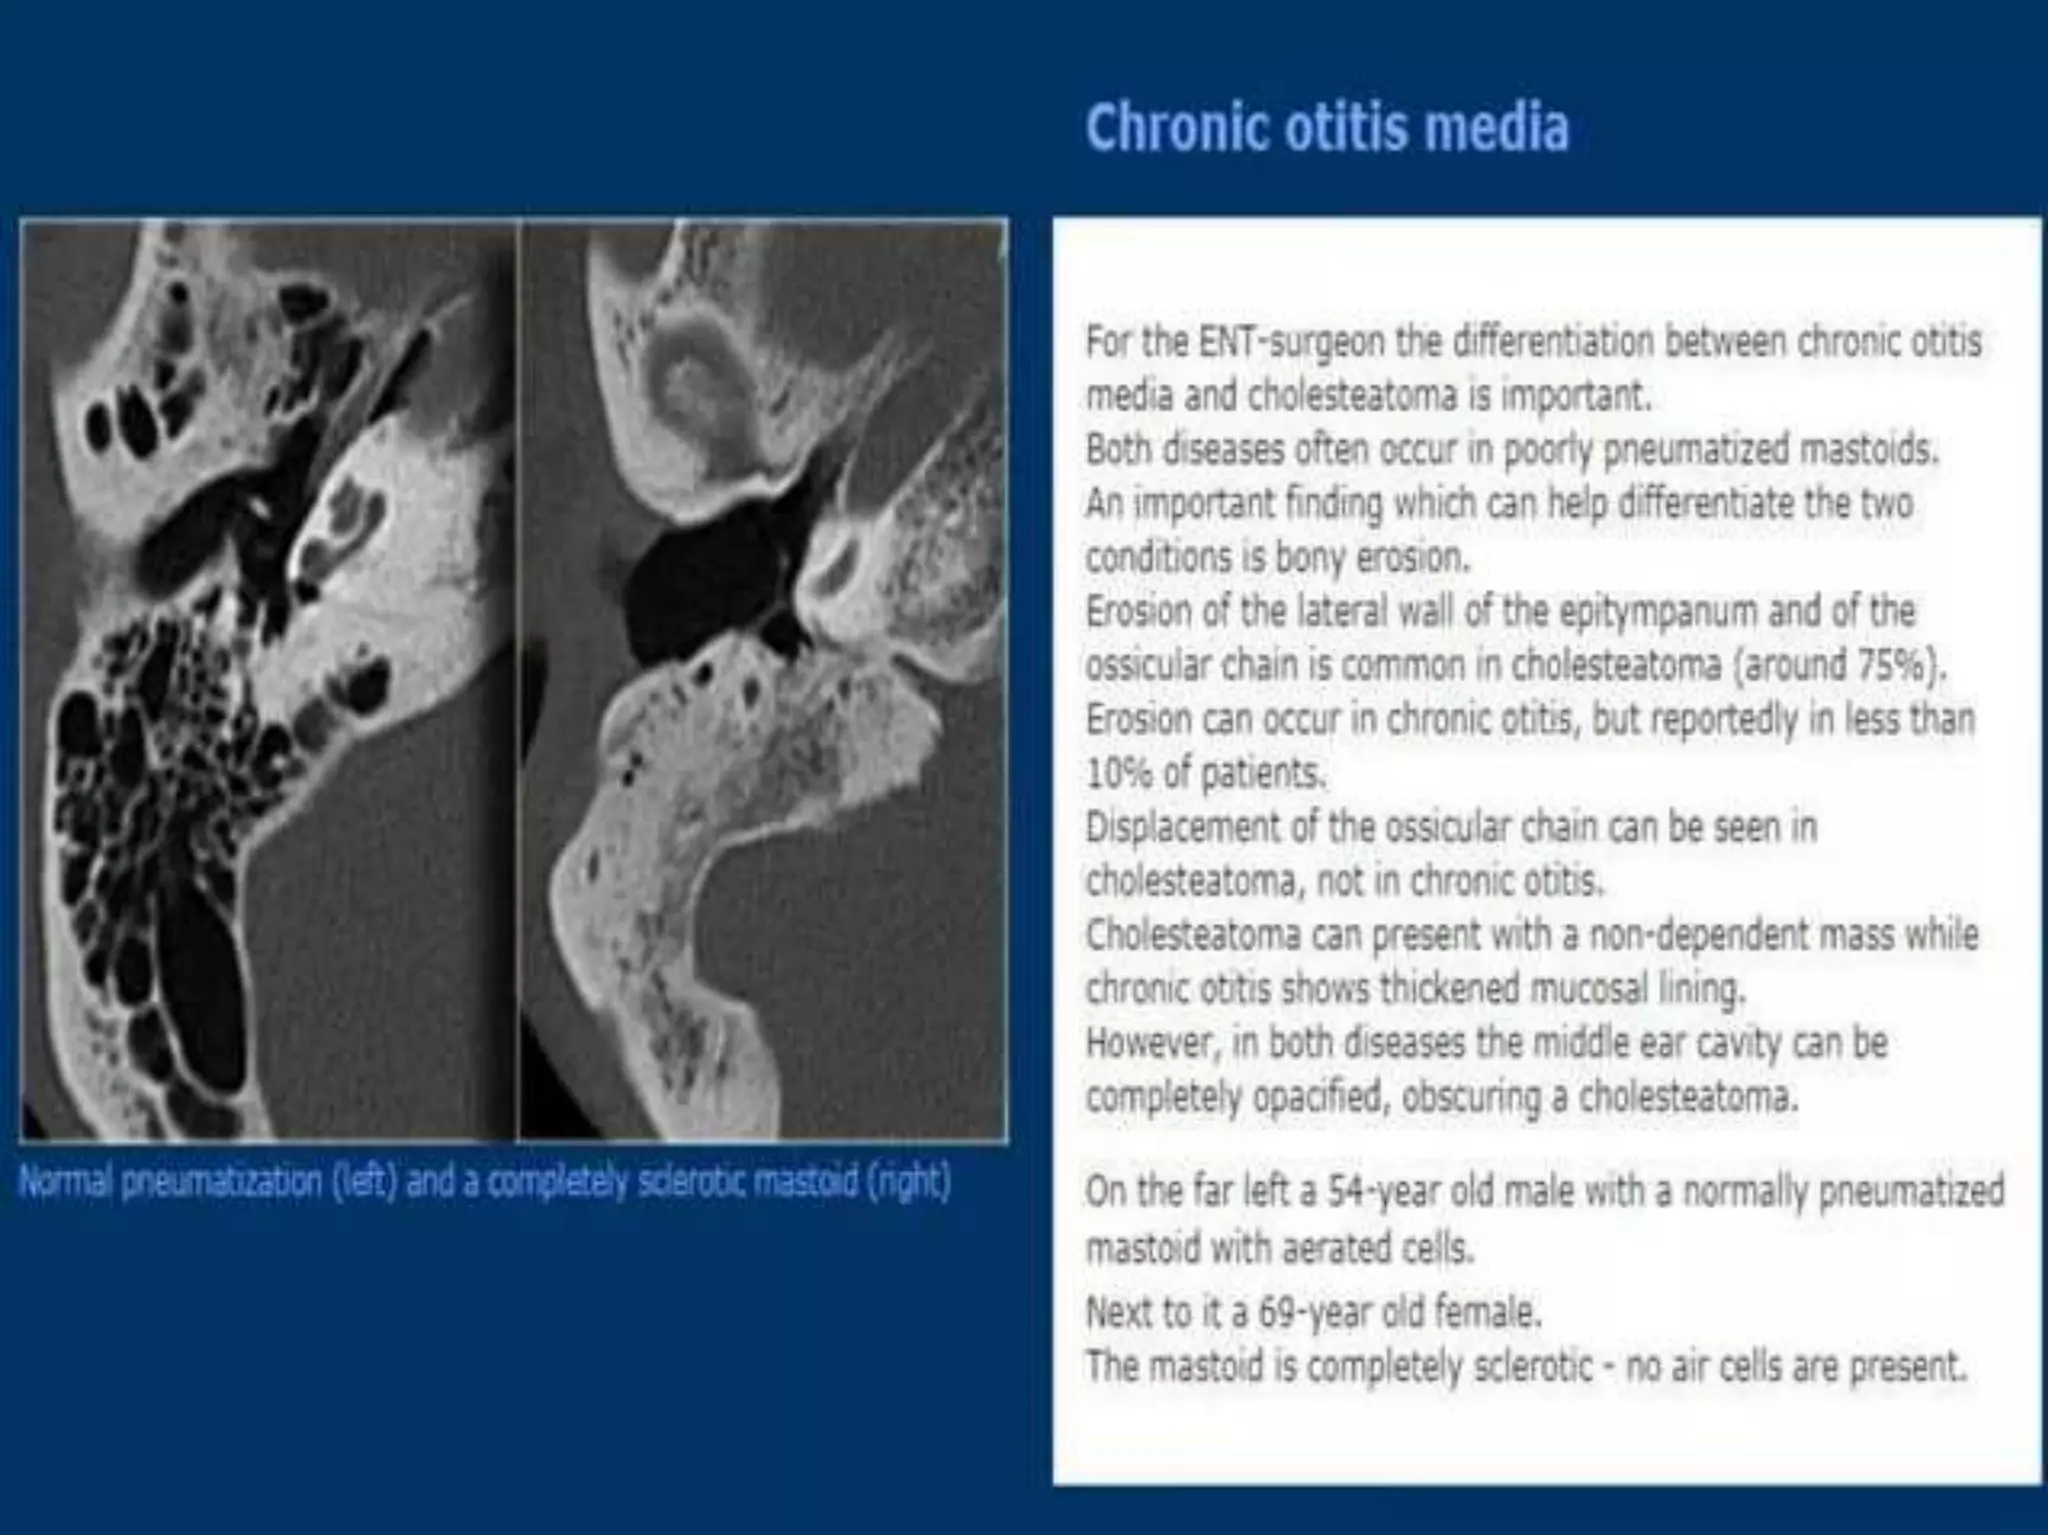

Chronic otitis media is a chronic inflammation of the middle ear and mastoid cavity that presents with recurrent ear discharge through a perforated eardrum. It has several subtypes depending on the state of the eardrum perforation and epithelium. It can be caused by prior acute otitis media, genetics, environment, eustachian tube issues, gastroesophageal reflux disease, craniofacial abnormalities, or immune deficiency.